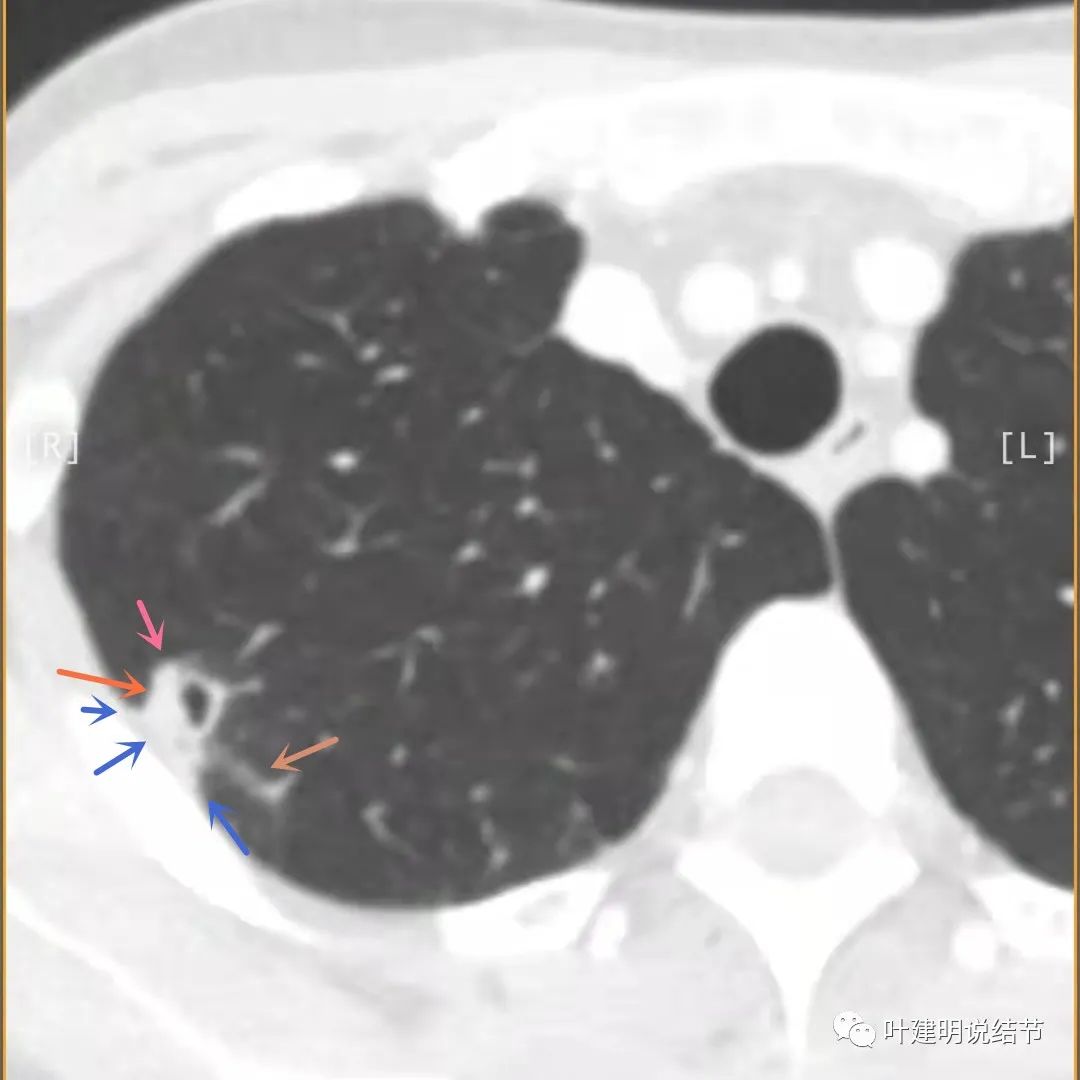

上面是她提供的病史资料,其中最重要的是PPD强阳性!其他主要看影像,我们先来看她2020年7月份的平扫片子(由于片子较多,详细展示是为了同道分析,我在影像特征描述上将只选取部分加以说明):

右肺尖偏实性结节(粉色箭头),邻近胸胸膜明显增厚不平,且广基附在胸壁上(蓝色箭头)

有卫星病灶(绿色箭头)

胸壁侧病灶较厚,模糊(蓝色箭头),仍见卫星灶(绿色箭头)

主病灶出现,粉色箭头示病灶密度较高,边上有磨玻璃影,甚淡(砖色箭头)

病灶有空洞(黄色箭头),主病灶边上见条索状高密度影(细红色箭头),邻近胸膜有粘连(蓝色箭头)